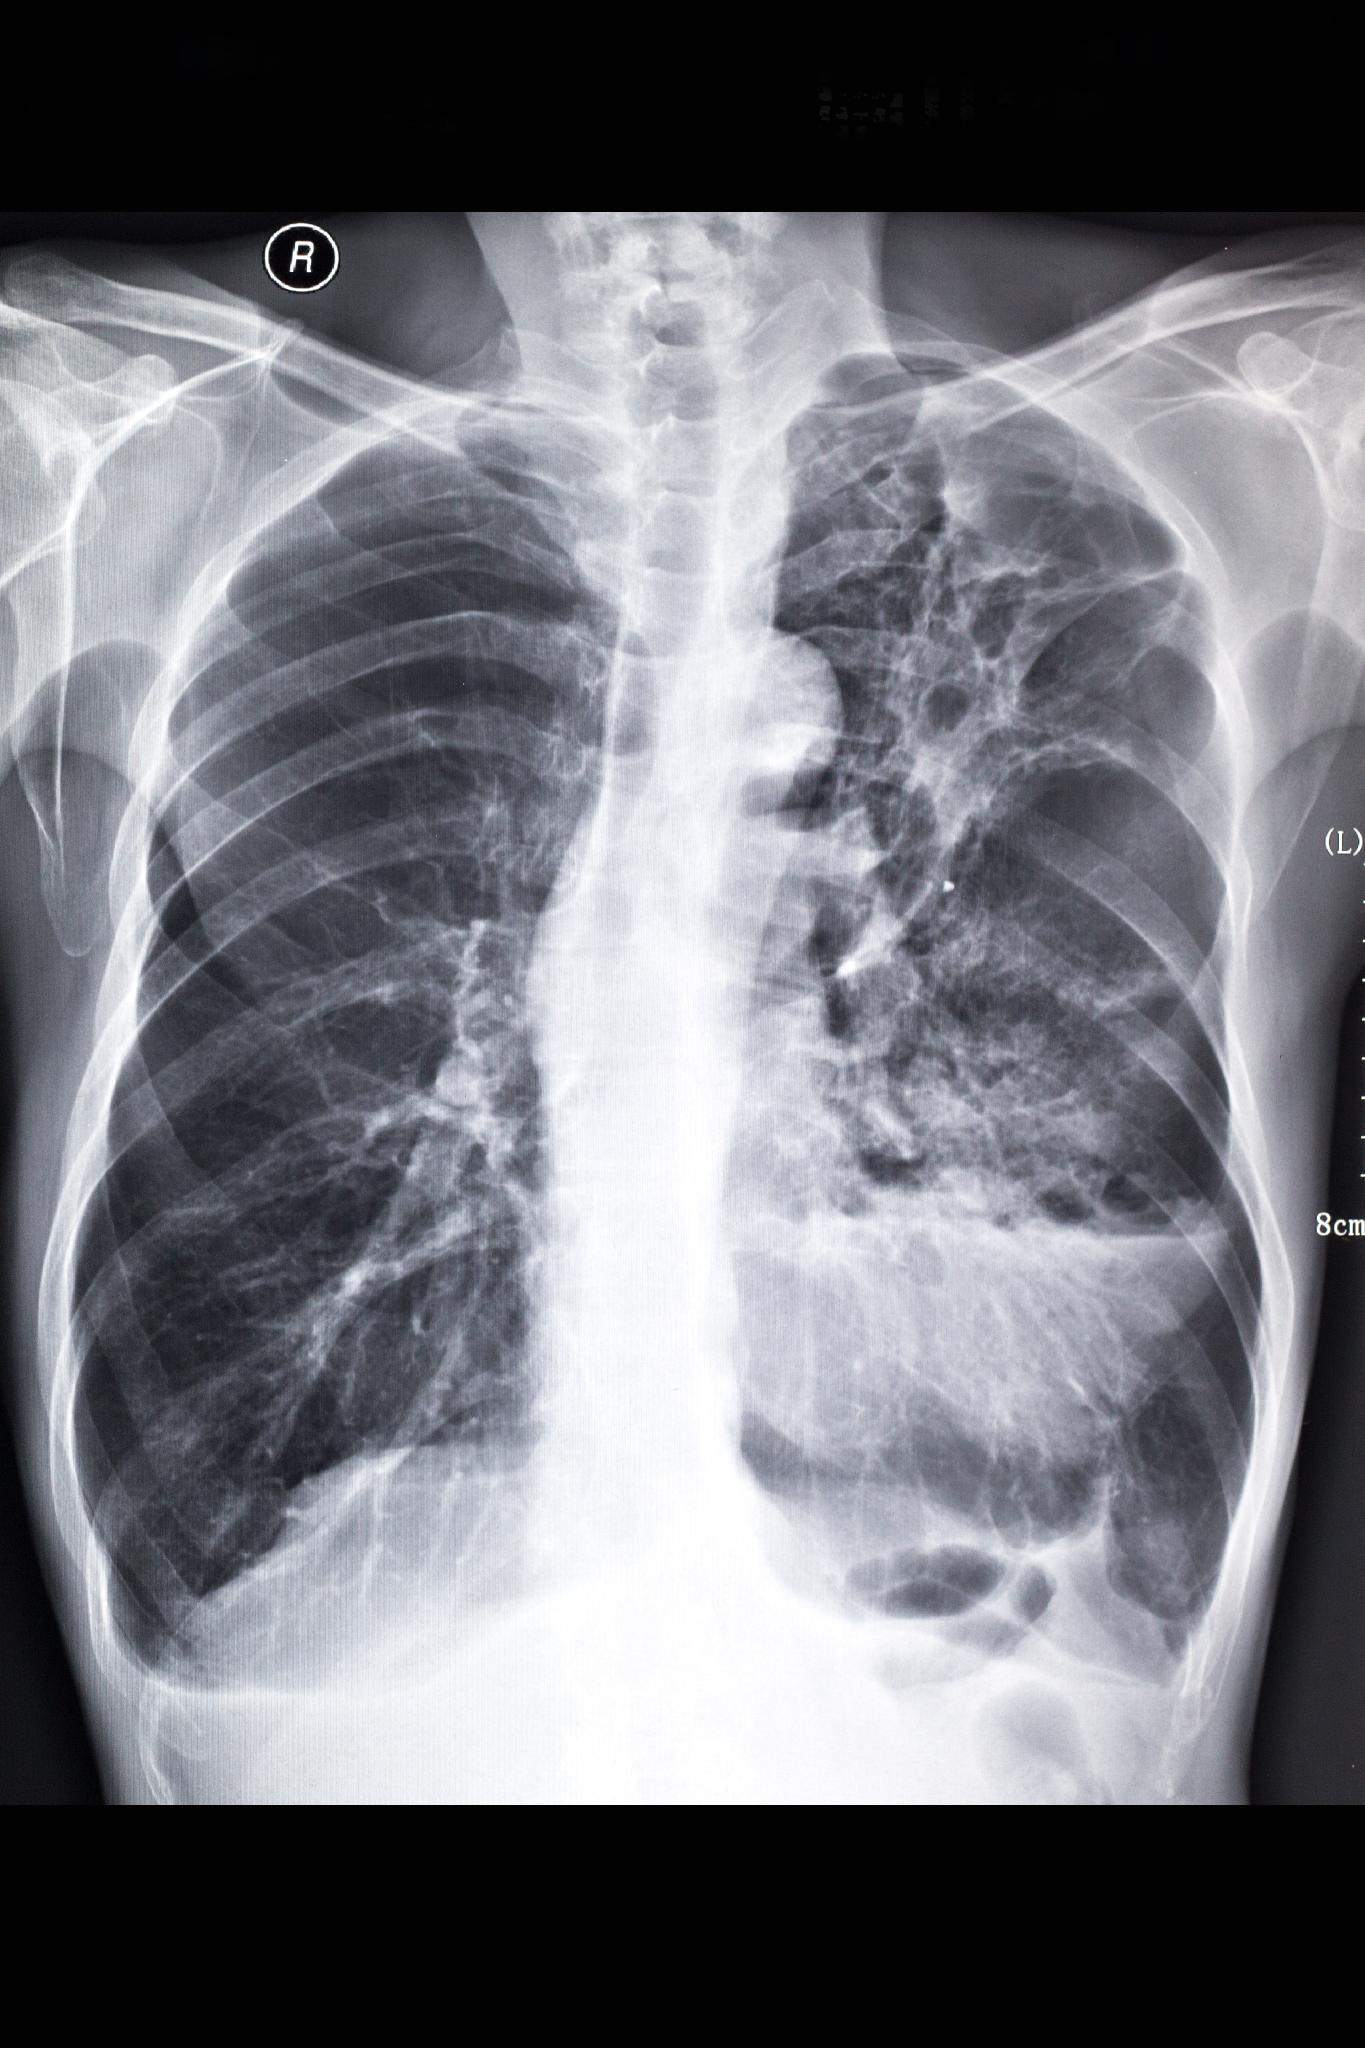

_左下肺肺纖維化影像

_右肺纖維化真實案例胸片

_中期肺纖維化X光